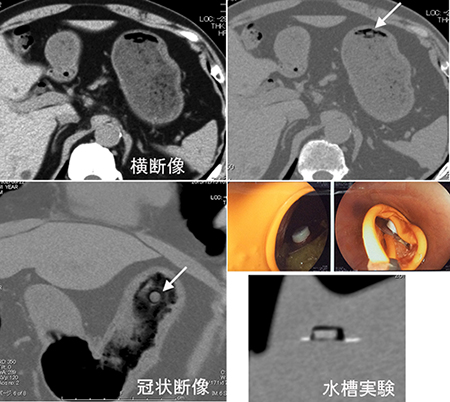

解答 解説 ある物 を誤飲したとして来院した80歳代女性 実践 画像

解答 解説 ある物 を誤飲したとして来院した80歳代女性 実践 画像

解答 解説 ある物 を誤飲したとして来院した80歳代女性 実践 画像

解答 解説 ある物 を誤飲したとして来院した80歳代女性 実践 画像

I M A Radiographer Radiotechnologist 私は放射線技師 ブログ